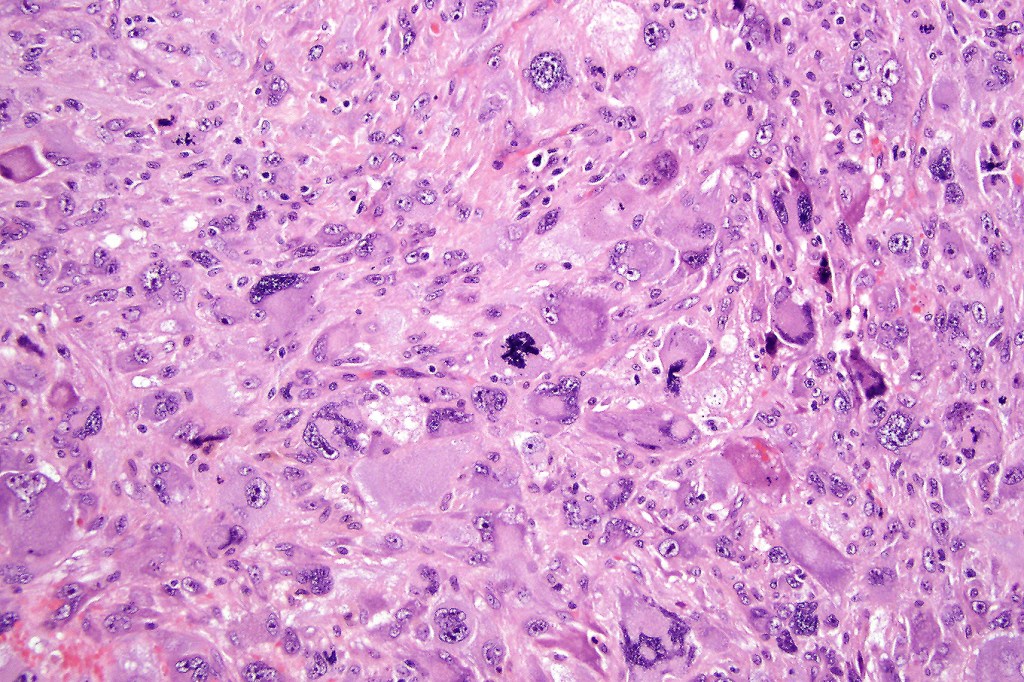

Carcinosarcoma

Cutaneous carcinosarcoma (metaplastic carcinoma, carcinoma with heterologous differentiation)

Histological features

•Osteoid

•Chondroid

•Smooth muscle

•MFH-like features with osteoclasts

•Neural differentiation